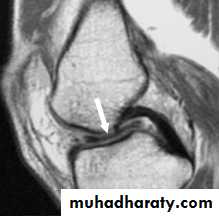

• MRI; good and accurate noninvasive technique specially if associated with arthroscopic findings.

Osteochondritis dissecans (splitting O.ch. of the knee):

its suggested to be caused by repeated trauma by the edge of the patella on full flexion that occurs on the lateral aspect of the medial femoral condyle (this site accounts for more than 80% of all cases).The disease pass in three stages:

• Avascular nonseperated segment with intact overlying cartilage.• Detached Undisplaced segment.

• Displaced segment, either incomplete or complete where it acts like a loose body leaving an ulcer called crater that later get fibrosed.

Diagnosis

X-ray:

It’s helpful at later stages. While isotope scanning and MRI can diagnose it earlier.

Arthroscopy: can prove diagnosis & sometimes used for treatment.